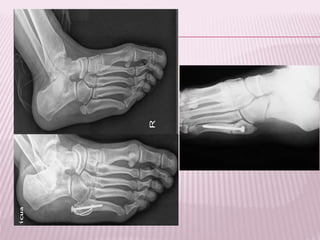

TIBIA Tobillo

PIE Calcáneo

Lisfranc (MTT)

Jones